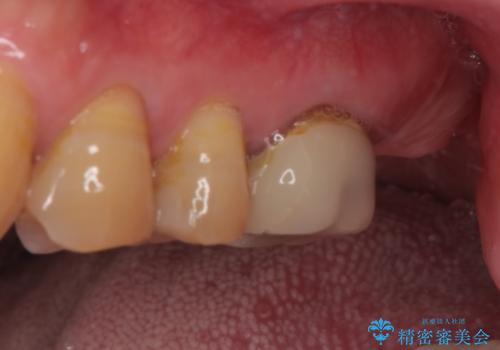

欠損した奥歯 インプラントによる補綴治療

- 破損したクラウンと、奥歯の欠損を気にして来院された患者様です。

奥歯の欠損部はインプラントによる補綴治療を、手前の破損したクラウンは作り替えをご希望でした。

しかしながら、レントゲンやCT画像から、手前の破損したクラウンの根尖部に大きな病変が認められ、インプラント埋入部にまで病変が及んでいることから、まずは手前の根管治療を行い、病変の正体を確認した後にインプラント埋入を行うこととしました。